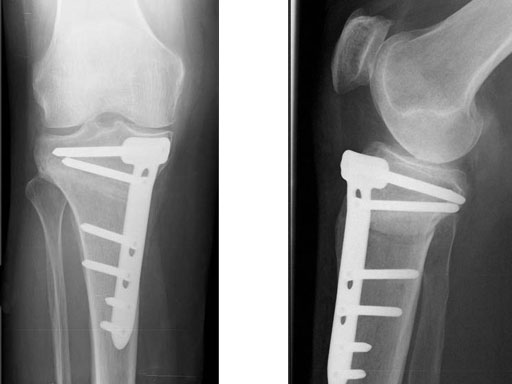

A 68-year-old female.

Case provided by Alex Staubli, Luzern, CH

The correction is planned on a long-leg standing x-ray. After surgery, the mechanical axis should pass through a point 63% on the lateral side of the total width of the tibial plateau in the frontal plane. A transverse or slightly oblique incision is used to avoid damage to the saphenous nerve. The distal fibers of the medial collateral ligament are detached from the tibia. Under fluoroscopic control, two wires are placed in the proximal tibia marking the transverse osteotomy plane. The cut usually starts at the upper margin of the pes anserinus and ends at the tip of the fibula on the lateral side. The wires are placed exactly parallel to the tibial plateau thus taking into consideration the individual tibial slope of the patient. An incomplete cut of the posterior two-thirds of the proximal tibia is performed with an oscillating saw guided by the wires. Continuous irrigation avoids burn injury to the bone. A second osteotomy is now performed in the anterior third of the tibia in an angle of 100 ending above the patellar tendon insertion. A smaller saw blade is used and the complete anterior cortex is cut exactly in the frontal plane. The osteotomy is now gradually opened by inserting flat chisels or a spreader-chisel into the posterior osteotomy cleft. This process may take some minutes and can usually be completed without fracture of the lateral cortex. A bone spreader is now placed in the posteromedial edge of the tibia and the chisels are removed. The leg is extended and the correction is checked with the fluoroscope. A long metal rod is placed between center of the hip joint and center of the ankle joint. The projection of this rod should be at the planned point of correction on the tibial plateau lateral of the midline. Eccentric collapse of the medial joint space may cause accidental overcorrection. In this case pressure on the foot may simulate loading and body weight. The correction can be fine-tuned by opening or closing the spreader. The TomoFix Medial Tibia Plate is now placed in a subcutaneous pocket. The implant is precontoured and usually fits well to the bone surface. The distance holders avoid compression of the medial collateral ligament and the pes anserinus. Three proximal bolts are placed near the subchondral sclerosis zone. The position of the bolts is adapted to the anatomy of the proximal tibia giving optimum purchase for the bolts. An oblique lag screw is inserted distal to the osteotomy. This screw in the first combination hole allows careful compression of the lateral osteotomy hinge and pretensioning of the implant. A stab incision is created on the shaft and the implant is fixed monocortically with bolts. The lag screw and the distance holders are replaced by bolts. The medial collateral ligament is released longitudinally to reduce medial compartment pressure and the wound is closed in layers. An overflow drain may be used. Clinical and experimental work has proven that when this technique is closely followed, corrections up to and over 15 mm can be performed without bone grafting or use of bone substitutes.

The patient is mobilized on crutches on day one after surgery. Partial weight bearing is allowed from the beginning. Biomechanical and RSA studies have proven that postoperative loading of the implant by body weight in standard partial weight bearing and early full weightbearing conditions did not cause loss of correction. Our group now allows the patients to walk without crutches as soon as the postoperative pain allows after this type of surgery. Members of the Knee Expert Group (KNEG) have presently implanted over 1,500 TomoFix medial tibia. The results are extremely positive in respect to osteotomy healing, implant failure, and surgical complications.